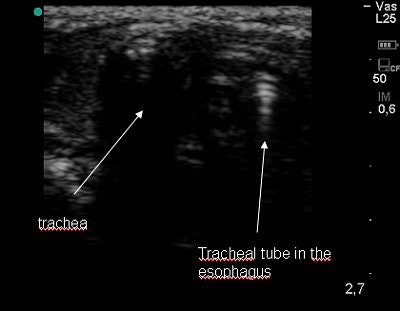

For the first prospective study, the researchers enrolled 11 children (mean age of 28 months) who were scheduled for surgery and suspected to have difficulties with intubation. After induction of anesthesia, a 5-10 MHz linear transducer on a Titan ultrasound scanner (SonoSite, Bothell, WA) was placed transversely on the anterior neck just superior to the suprasternal notch. Direct laryngoscopy was performed and tracheal intubation took place. In instances of poor glottis visualization, tracheal catheterization was used. Tube placement confirmation was evaluated by ultrasound, auscultation, and end-tidal capnography.

According to the results, tracheal intubation was successful on the first attempt in seven cases. In the other four cases, intubation was successful on the second attempt or tracheal catheterization was required. One esophageal intubation occurred but it was immediately visualized on ultrasound. In all cases, tracheal tube placement was confirmed by sonography before end-tidal capnography.

Ultrasound's accuracy "in determining tube position seems to be an excellent and faster than any other method," the authors concluded.